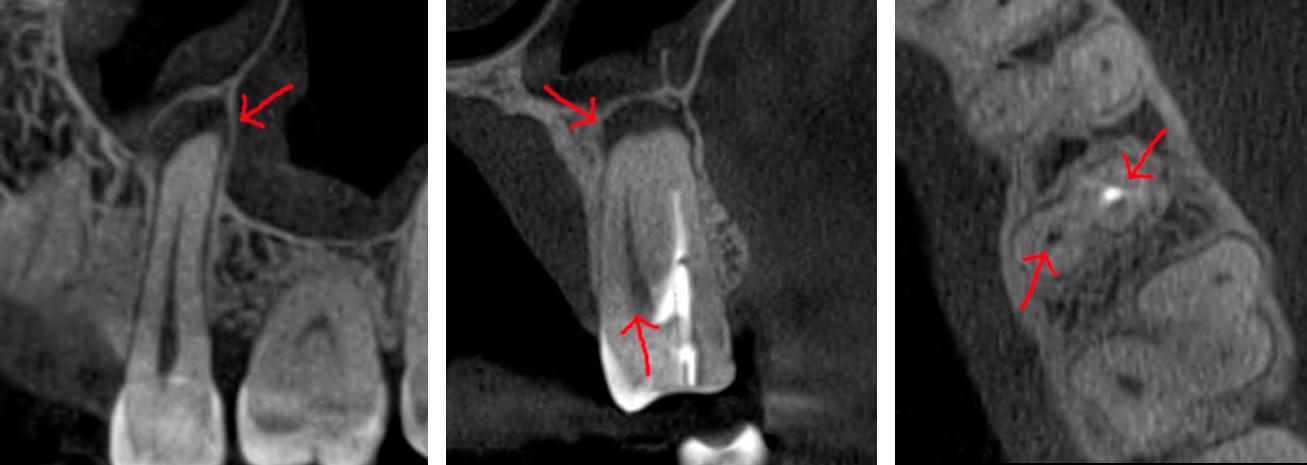

Коли коріння «ховає сюрпризи» - Корені зубів часто мають складну кривизну, гачкоподібні закручення або розгалуження, які на звичайному 2D-знімку накладаються один на одного, створюючи ілюзію прямого каналу. На плоскій картинці неможливо побачити реальний об'єм та напрямок вигину, що критично важливо при видаленні «зубів мудрості» або ендодонтичному лікуванні. КТ MyRay дає змогу лікарю заздалегідь побачити 3D-геометрію кожного кореня, оцінити його близькість до нижньощелепного нерва чи гайморової пазухи та підібрати правильну тактику роботи. Це мінімізує ризики поломки інструменту в каналі або травмування сусідніх структур, перетворюючи складну хірургію на прогнозовану процедуру.

Часто причиною зубного болю є гайморит, і навпаки — причиною запалення пазух є хворий зуб. На звичайному знімку пазуха виглядає як темна пляма. На КТ ми бачимо стан слизової, наявність кіст або сторонніх тіл (наприклад, залишків пломбувального матеріалу), що критично важливо для правильного діагнозу.